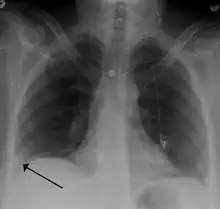

A Hampton hump in a person with a right lower lobe pulmonary embolism

• Chest X-rays are often done on people with shortness of breath to help rule-out other causes, such as congestive heart failure and rib fracture. Chest X-rays in PE are rarely normal,[68] but usually lack signs that suggest the diagnosis of PE (for example, Westermark sign, Hampton's hump).